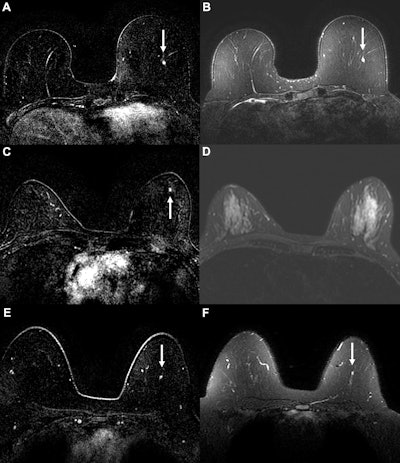

Example cancer examinations where the AI suspicion score prompted triage to abbreviated breast MRI, but readers still assessed the abbreviated MRI exam as suspicious. Axial (A) dynamic contrast-enhanced (DCE) and (B) fat-saturated T2-weighted MRI scans in a 58-year-old woman with a 0.3-cm enhancing focus (arrow) in the left breast. The AI tool generated a suspicion score of 0.68 (43rd percentile of suspicion score), prompting triage at the 50% threshold. For abbreviated MRI, readers gave the examination a suspicious assessment, but for the full MRI protocol, readers missed the suspicious finding, possibly owing to its T2 hyperintensity. The original radiologist also gave a benign assessment, but cancer was diagnosed six months later via mammography, with calcifications indicating ductal carcinoma in situ. Axial (C) DCE and (D) fat-saturated T2-weighted MRI scans in a 51-year-old woman with a 0.3-cm enhancing focus (arrow in C) in the left breast. The AI tool generated a suspicion score of 0.42 (17th percentile), prompting triage at the 50% threshold. For both abbreviated and full MRI, readers gave the examination a suspicious assessment, although the original radiologist report gave a benign assessment. Cancer was diagnosed six months later via mammography. Biopsied calcifications indicated ductal carcinoma in situ. Axial (E) DCE and (F) fat-saturated T2-weighted MRI scans in a 49-year-old woman with a 0.4-cm enhancing focus (arrow) in the left breast. The AI tool generated a suspicion score of 0.62 (37th percentile), prompting triage at the 50% threshold. The lesion was missed by readers at both abbreviated and full MRI. The patient was diagnosed with invasive ductal carcinoma six months after an abnormal contrast-enhanced mammogram.RSNA